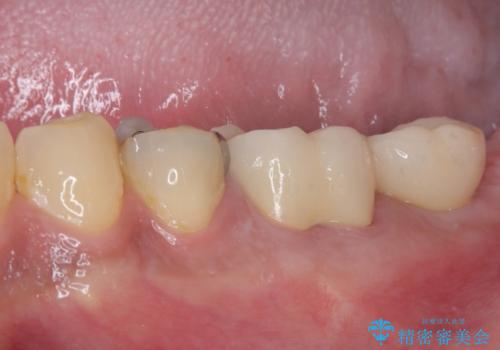

根管治療後に痛みは一次消退しましたが、半年ほど経過しても病変は改善しておらず、歯根が破折している状態となっていました。

歯根が破折した歯は抜歯となるため、抜歯して病変の部分に骨が回復するのを待って、インプラントによる補綴治療を行うこととしました。